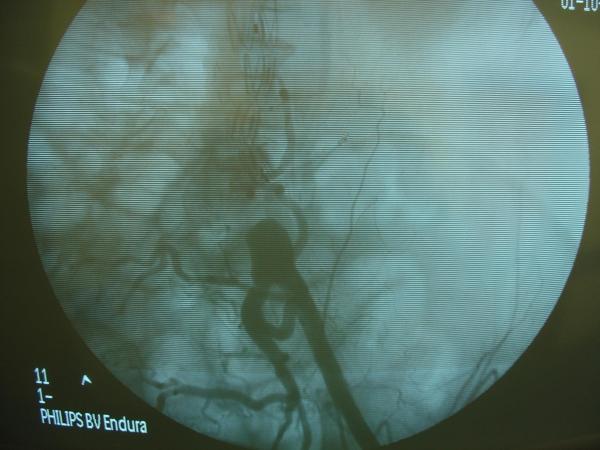

Endovascular repair of anastomotic abdominal aortic aneurysm, after aortobifemoral bypass

Vascular Clinic, Naval and Veterans Hospital of Athens

AVEM2009-Thessaloniki